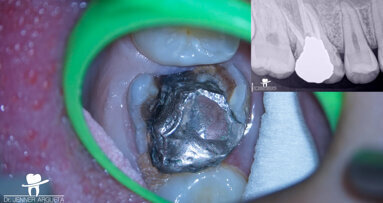

A 50-year-old patient with non-contributory systemic disease presented with the main complaint of pain on mastication. He reported having had a direct restoration on the mandibular left first molar six months earlier. On clinical and radiographic examination, a large, overextended amalgam Class II filling was observed as well as a J-shaped radiolucency on the distal aspect of the tooth (Fig. 1). A buccal swelling oriented distally was also present, as were characteristics of occlusal wear compatible with bruxism on the patient’s dentition. The tooth had pain on percussion and responded negatively to electrical and thermal stimulus tests. When probing in the region of the abscess, a 9 mm isolated pocket was identified (Fig. 2). The tooth was diagnosed with pulpal necrosis and periapical abscess and a suspected VRF. To confirm the presumptive diagnosis, an access cavity was prepared under dental dam isolation and under the dental operating microscope. When the previous restoration was removed, a longitudinal fissure line was detected on the distal aspect of the pulpal floor at higher magnification (10×).

Fig. 1a

Fig. 1b

Fig. 2